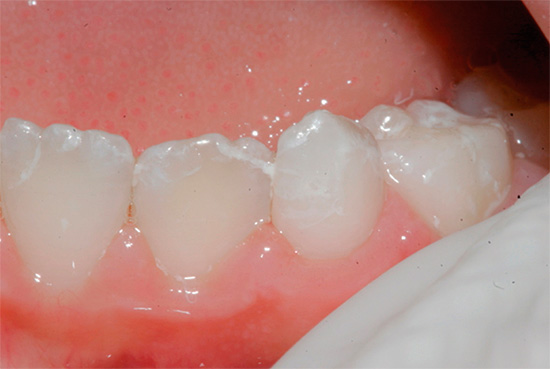

L'ispezione visiva dei denti è il modo principale per identificare una situazione cariogena nella cavità orale. La carie è caratterizzata dal fatto che in quasi tutte le fasi del suo corso, cambia il colore dello smalto dei denti. Anche nella fase spot, quando la dentina non è ancora interessata, lo smalto cessa di essere liscio e lucido e il dentista attento nota facilmente un tale cambiamento.

In fasi successive, determinare la carie con un semplice esame è ancora più semplice: porta alla comparsa di punti neri e marrone scuro sui denti o quando la dentina è danneggiata, sotto lo smalto sono visibili cavità scure.

Non sorprende, nella maggior parte dei casi, la diagnosi visiva della carie dentale può rivelare la maggior parte delle aree interessate. Con lei, il dentista esamina attentamente i denti da diversi lati con uno specchio. Inoltre, il medico può eseguire una sonda sonda: in luoghi dello sviluppo precoce del processo cariato, si avverte chiaramente la rugosità della superficie dello smalto.